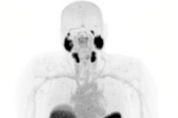

SECuRE trial to continue with no modifications to protocol follo…

HIGHLIGHTS Following an interim data review of the Cohort Expansion Phase (Phase II) of the SECuRE trial, the Safety Review Committee (SRC) confirms the trial will continue with no modifications to the protocol. Patient population With the SECuRE trial continuing to recruit, a total of nine participants who had evaluable data by the 25th of November 2025 were included in the interim assessment by the SRC, with the majority of participants receiving at least two cycles of 8 GBq of 67Cu-SAR-bisPSMA each by the data cut-off date. Seven participants received